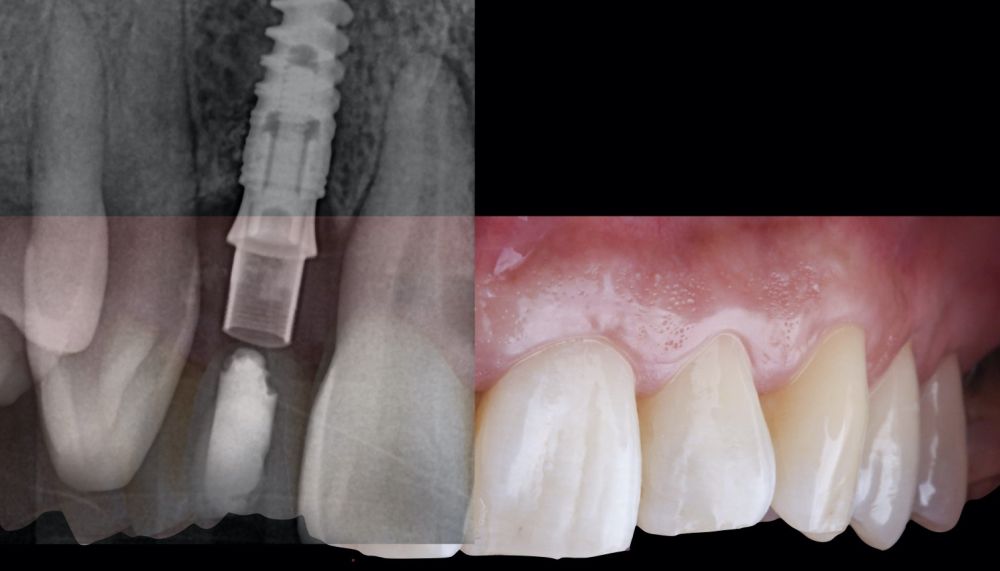

-Fase II: la cicatrización transcurrió sin complicaciones. Tras 5 meses de la cirugía de preservación alveolar, se planificó la cirugía implantológica guiada en posición 1.2 (Figura 2). Para ello, se utilizaron un archivo DICOM procedente de la tomografía computarizada de haz cónico (CBCT) y el archivo STL procedente del escaneado mediante un escáner óptico intraoral. Con esta información se construyó una férula quirúrgica de soporte dental (Figura 3). La férula quirúrgica se ancló sobre los dientes y guió la realización del lecho implantario y la colocación del implante. La técnica quirúrgica de cirugía guiada consistió en una cirugía con colgajo, preparando e insertando el implante (3,5 x 11,5 mm) según el protocolo estandarizado de cirugía guiada Nobel Active® (Nobel Biocare AB, Gothenburg, Sweden). Una vez colocado el implante 1.2, se obtuvo un injerto gingival compuesto de epitelio y tejido conectivo de la mucosa masticatoria palatina. A continuación, se realizó la desepitelización de la capa superficial de dicho injerto fuera de boca mediante una hoja de bisturí 15C con la finalidad de obtener un injerto de tejido conectivo de la capa subyacente18.

El injerto desepitelizado se insertó y posicionó por vestibular y oclusal mediante un punto colchonero horizontales utilizando sutura 5-0 no reabsorbible (Figura 4)19.